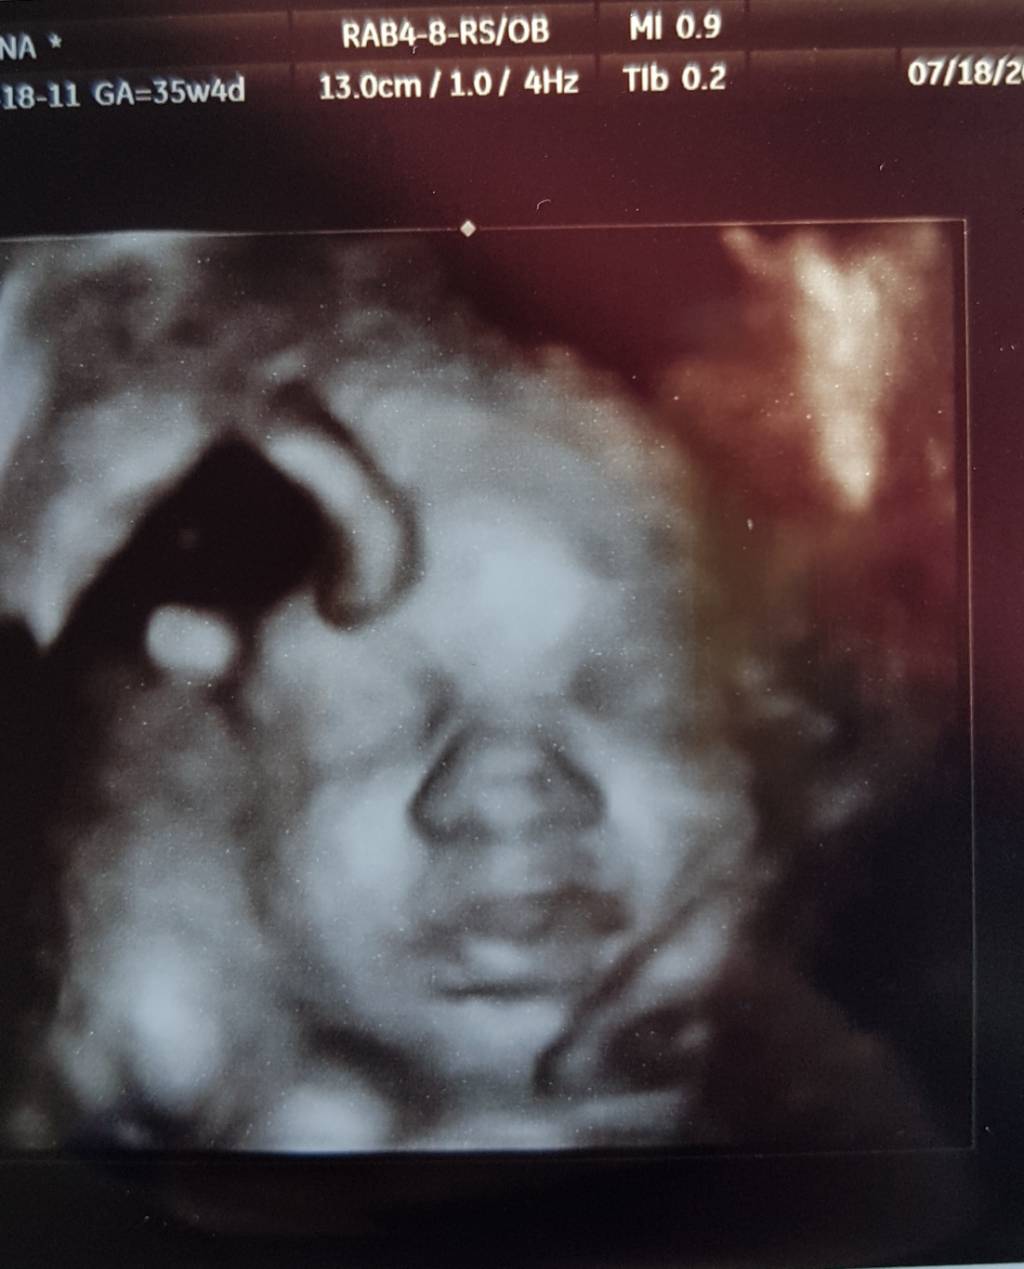

Zobacz załącznik 815200

A Michaś już jest taki duży